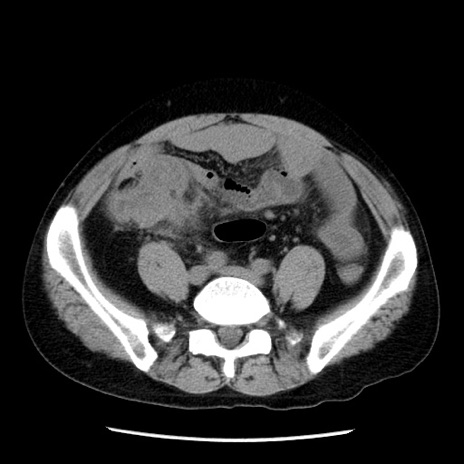

冠状断像

【症例】40歳代男性

【現病歴】2日前から胃痛あり。徐々に周期的な激痛に変化した。本日になっても激痛があるため受診。

【身体所見】意識清明、BT 38-39℃台あり、腹部:膨満、やや硬、右下腹部に圧痛あり。

【データ】WBC 8500、CRP 23.26